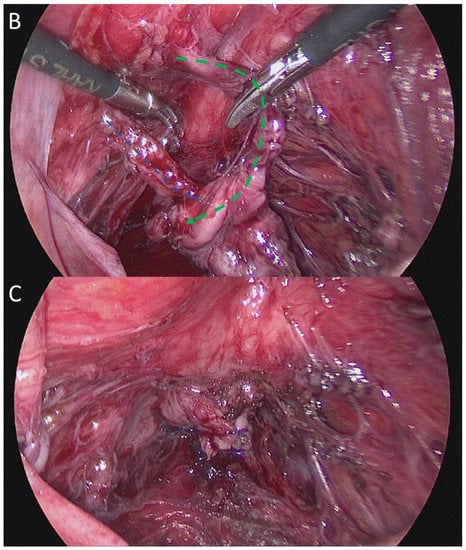

2. Case Presentation